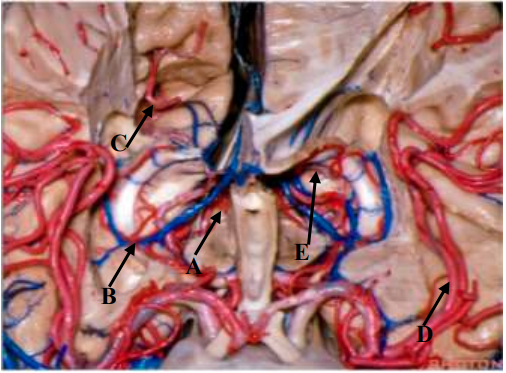

Qual seta aponta para o Ponto Coroideo Inferior?

Provas